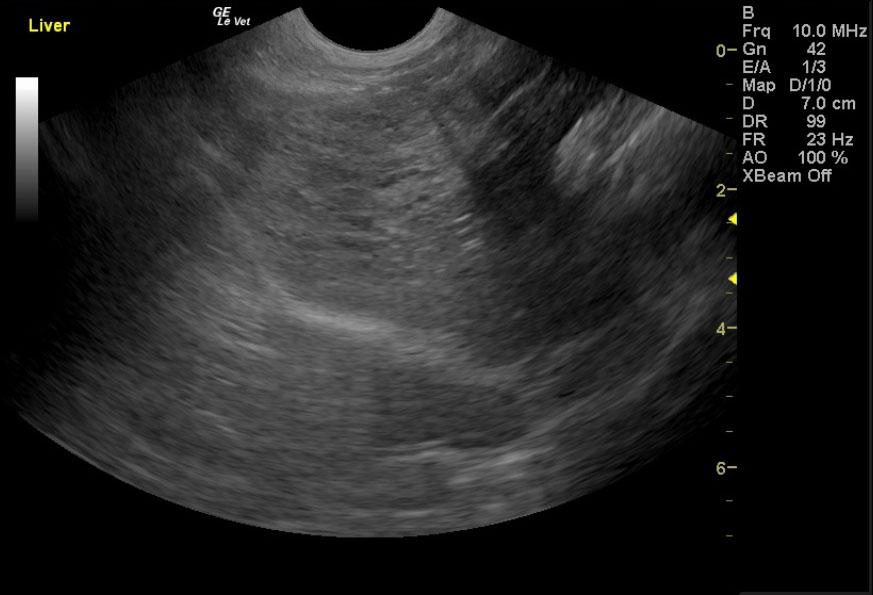

A 17-year-old neutered male DSH cat was presented to the emergency clinic with open-mouth breathing suspected to be secondary to stress/pain as the patient improved on analgesics. On a prior physical examination, an abdominal mass had been palpated.